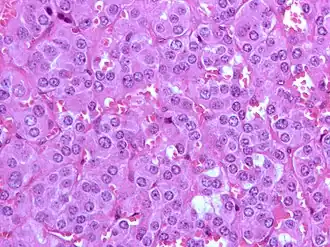

Feocromocitomul reprezintă o tumoare endocrină a medulosuprarenalei (celulele cromafine), fiind caracterizat prin secreția masivă de catecolamine (în special noradrenalină). Feocromocitomul primar extrasuprarenalian (ganglioni simpatici din sistemul nervos vegetativ) este cunoscut ca paragangliom (aproximativ 10%-15% din cazuri de feocromocitom). Numai 10% din tumorile medulosuprarenaliene sunt maligne.